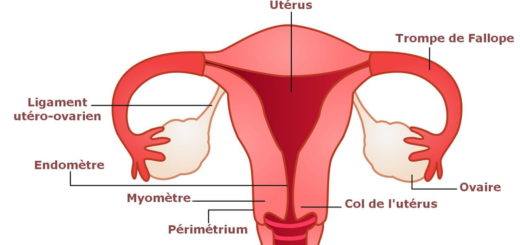

L’utérus est cette poche ou ce nid où l’embryon s’installera et s’y développera pour devenir fœtus et donner le bébé. La qualité de l’utérus détermine donc le fait que la grossesse de la femme...